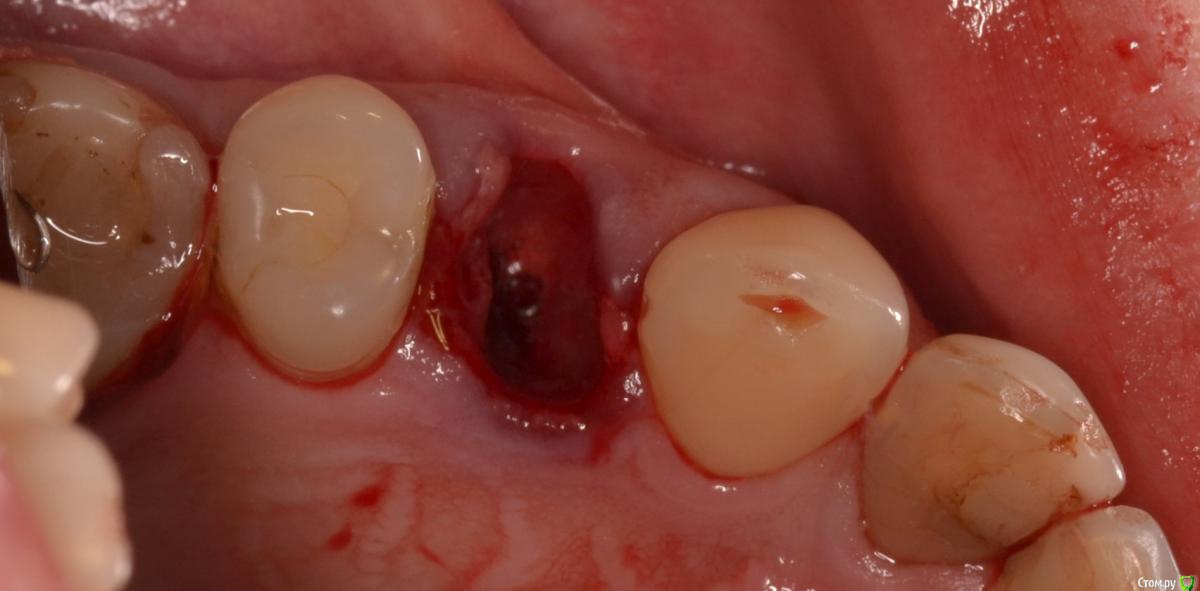

Военный Врач Опубликовано 5 апреля, 2016 Поделиться Опубликовано 5 апреля, 2016 Удалили и прикрутили. между имплантацией и снятием швов 9 суток. лунку закрывал тканями с бугра 18 Ссылка на комментарий

Военный Врач Опубликовано 6 апреля, 2016 Автор Поделиться Опубликовано 6 апреля, 2016 Александр почему выбрали обычный винт а не эволюшн?Я на них при одномоментной очень приличные торки получаю.в запаре посмотрел на эволюшен, а взял лико. корень удалял 45 минут, упарился Ссылка на комментарий